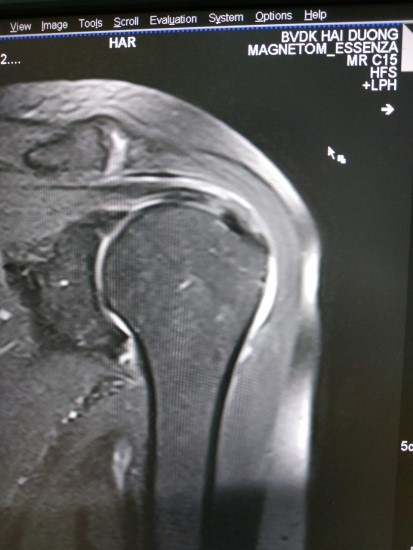

Hình ảnh điển hình tổn thương GCX

Hình 4. Hình ảnh tổn thương gân cơ trên gai

Hình 5. Hình ảnh rách bán phần(A), rách hoàn toàn(B)